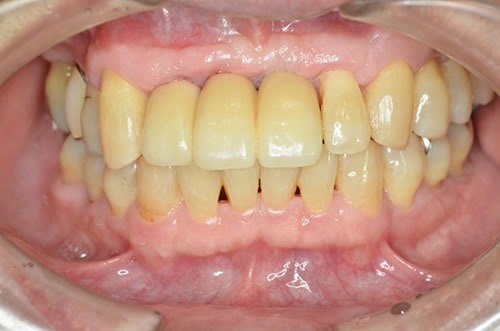

■治療後

患者さんも、ご紹介いただいた先生にも喜んでいただきました。